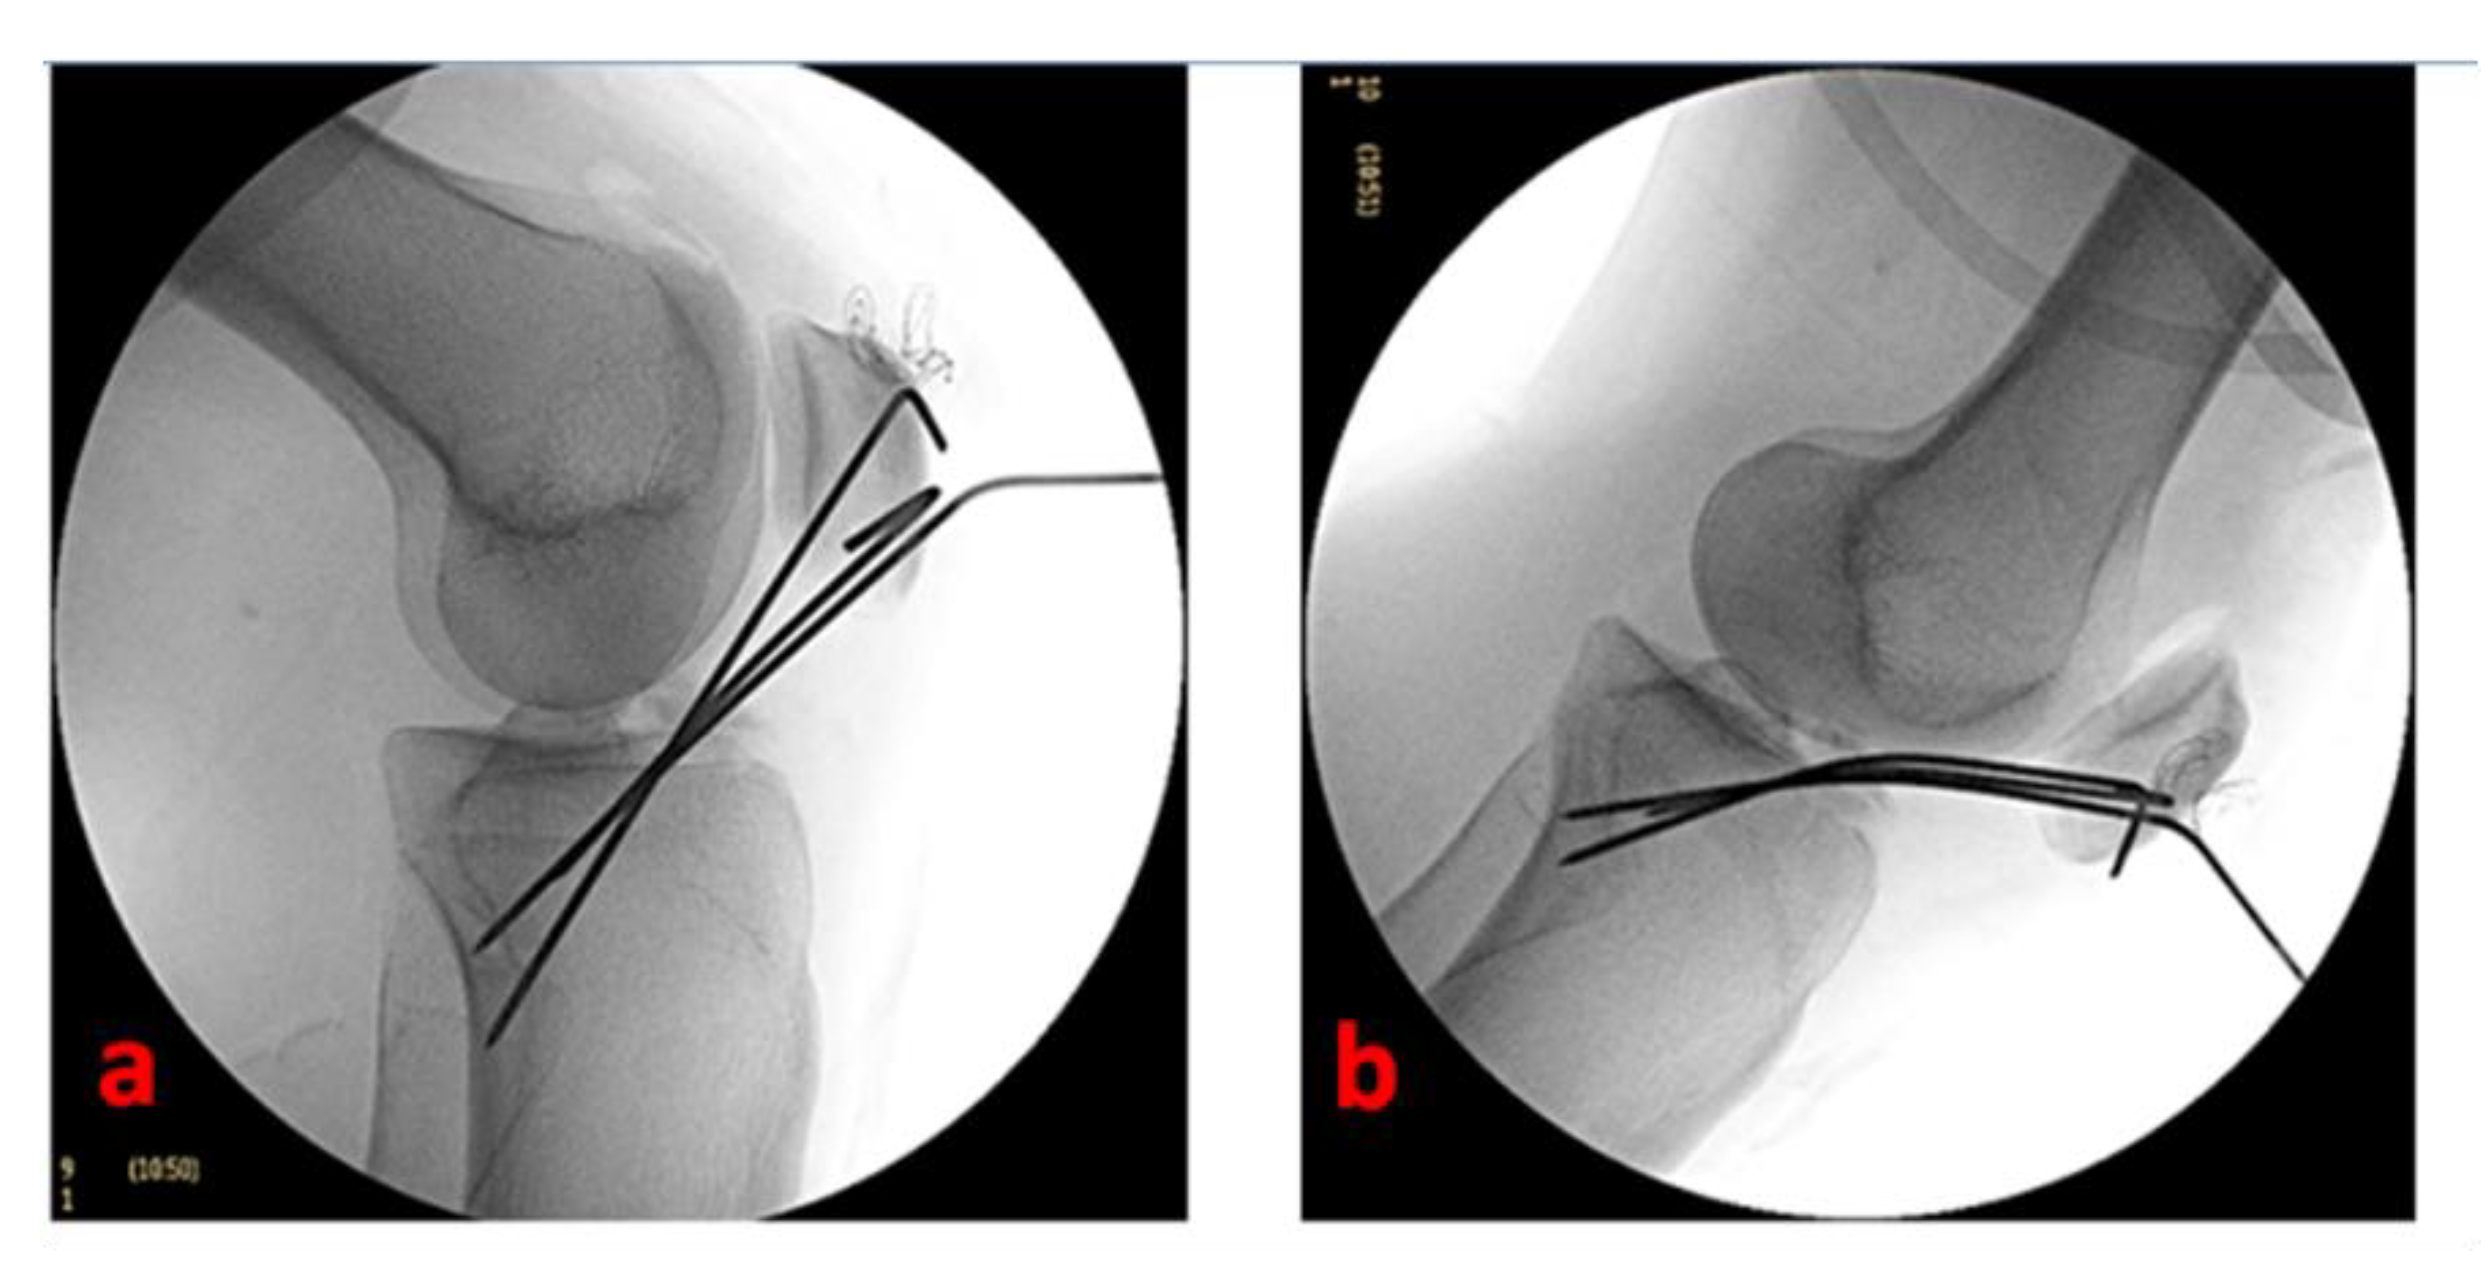

2.3. Approach and Fracture Fixation